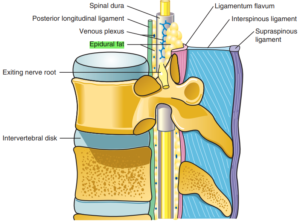

نخاع در تمام طول ستون فقرات، در داخل مهرهها و توسط سه لایه محافظ احاطه شده است.

خارجیترین لایه، دورا (Dura) نام دارد.

به فضای بین این لایه و سطح داخلی مهرههای ستون فقرات، فضای اپیدورال گفته میشود که با بافت چربی و عروق کوچک پر شده است.

در تصاویر زیر، این فضا با هایلایت سبز مشخص شده است.

به دلیل نزدیکی فضای اپیدورال به نخاع، میتوان برای بلاک اعصاب نخاعی (اعصابی که مستقیماً از نخاع خارج میشوند) داروهای بیحسی را به داخل این فضا تزریق کرد.

پس از تزریق، دارو بهصورت موضعی پخش شده و اعصاب نخاعی مجاور را بلاک میکند.

به دلیل نزدیکی این لایه با نخاع می توان برای انجام بلاک اعصاب نخاعی (اعصابی که مستقیما از نخاع خارج می شوند) از تزریق دارو های بی حسی به داخل این فضا استفاده نمود. بعد از تزریق دارو های بی حسی به این فضا، با پخش شدن موضعی دارو ها اعصاب نخاعی مجاور محل تزریق بلاک می شوند.